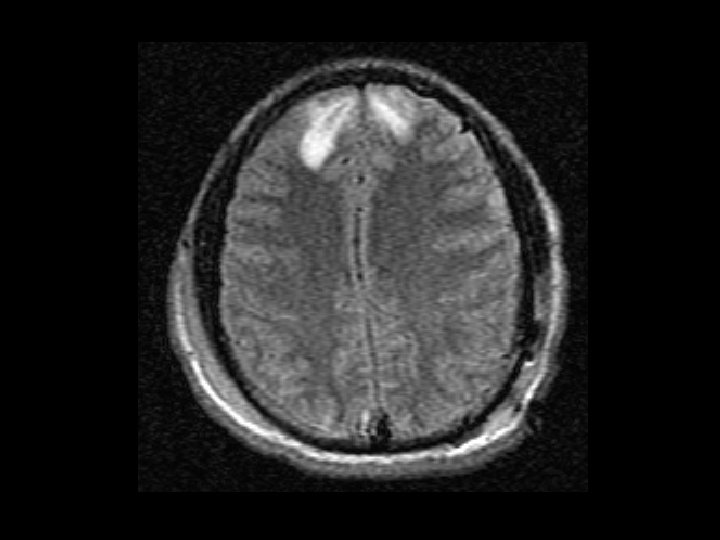

Tụ máu dưới màng cứng • Chảy máu giữa màng cứng và não – Thường gặp hơn tụ máu ngoài màng cứng – 30% bệnh nhân CTSN có tụ máu dưới màng cứng • CT: khoảng tụ máu hình liềm • Có thể gặp cấp tính, bán cấp hoặc mãn tính – Bán cấp hoặc mãn tính diễn biến nhiều ngày/tuần sau chấn thương

Tụ máu dưới màng cứng • Tăng nguy cơ ở người già (cơ chế chấn thương không nghiêm trọng) – Não teo nhỏ đi theo lứa tuổi gây giãn các tĩnh mạch cầu nối ở khoảng dưới màng cứng • Có thể tăng dần kích thước (chậm hơn máu tụ ngoài màng cứng) • Phẫu thuật dẫn lưu nếu tổn thương gây choán chỗ và đè đẩy

Chẩn đoán • MRI: – Tốt hơn CT – Có thể phát hiện dấu hiệu tổn thương sợi trục lan tỏa và các chấn thương không phát hiện được trên CT scan – Không là biện phát chẩn đoán thường quy • 30 – 45 phút để chụp • Đắt tiền và không phổ biến